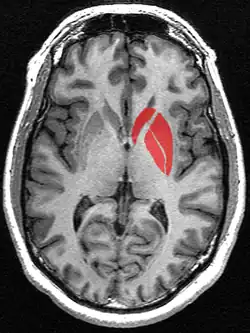

![]() Striatum shown in green with other basal ganglia and thalamus. Small region in yellow is the amygdala | |